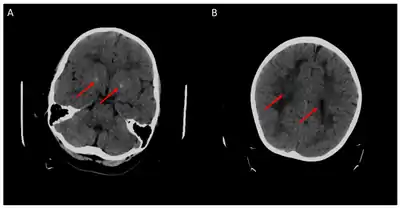

Наиболее ярко ЦФН проявляется при мутациях гена FOLR1, отвечающего за доставку фолатов в центральную нервную систему[3][4]. Ребенок с мутацией рождается здоровым. Заболевание дебютирует чуть позже - в раннем детском возрасте - такими симптомами, как задержка психомоторного развития, атаксия, тремор, хорея, миоклонические приступы. На МРТ-снимках может наблюдаться гипомиелинизация. При немедленном назначении фолиниевой кислоты можно добиться значительного улучшения состояния.

Иллюстрации